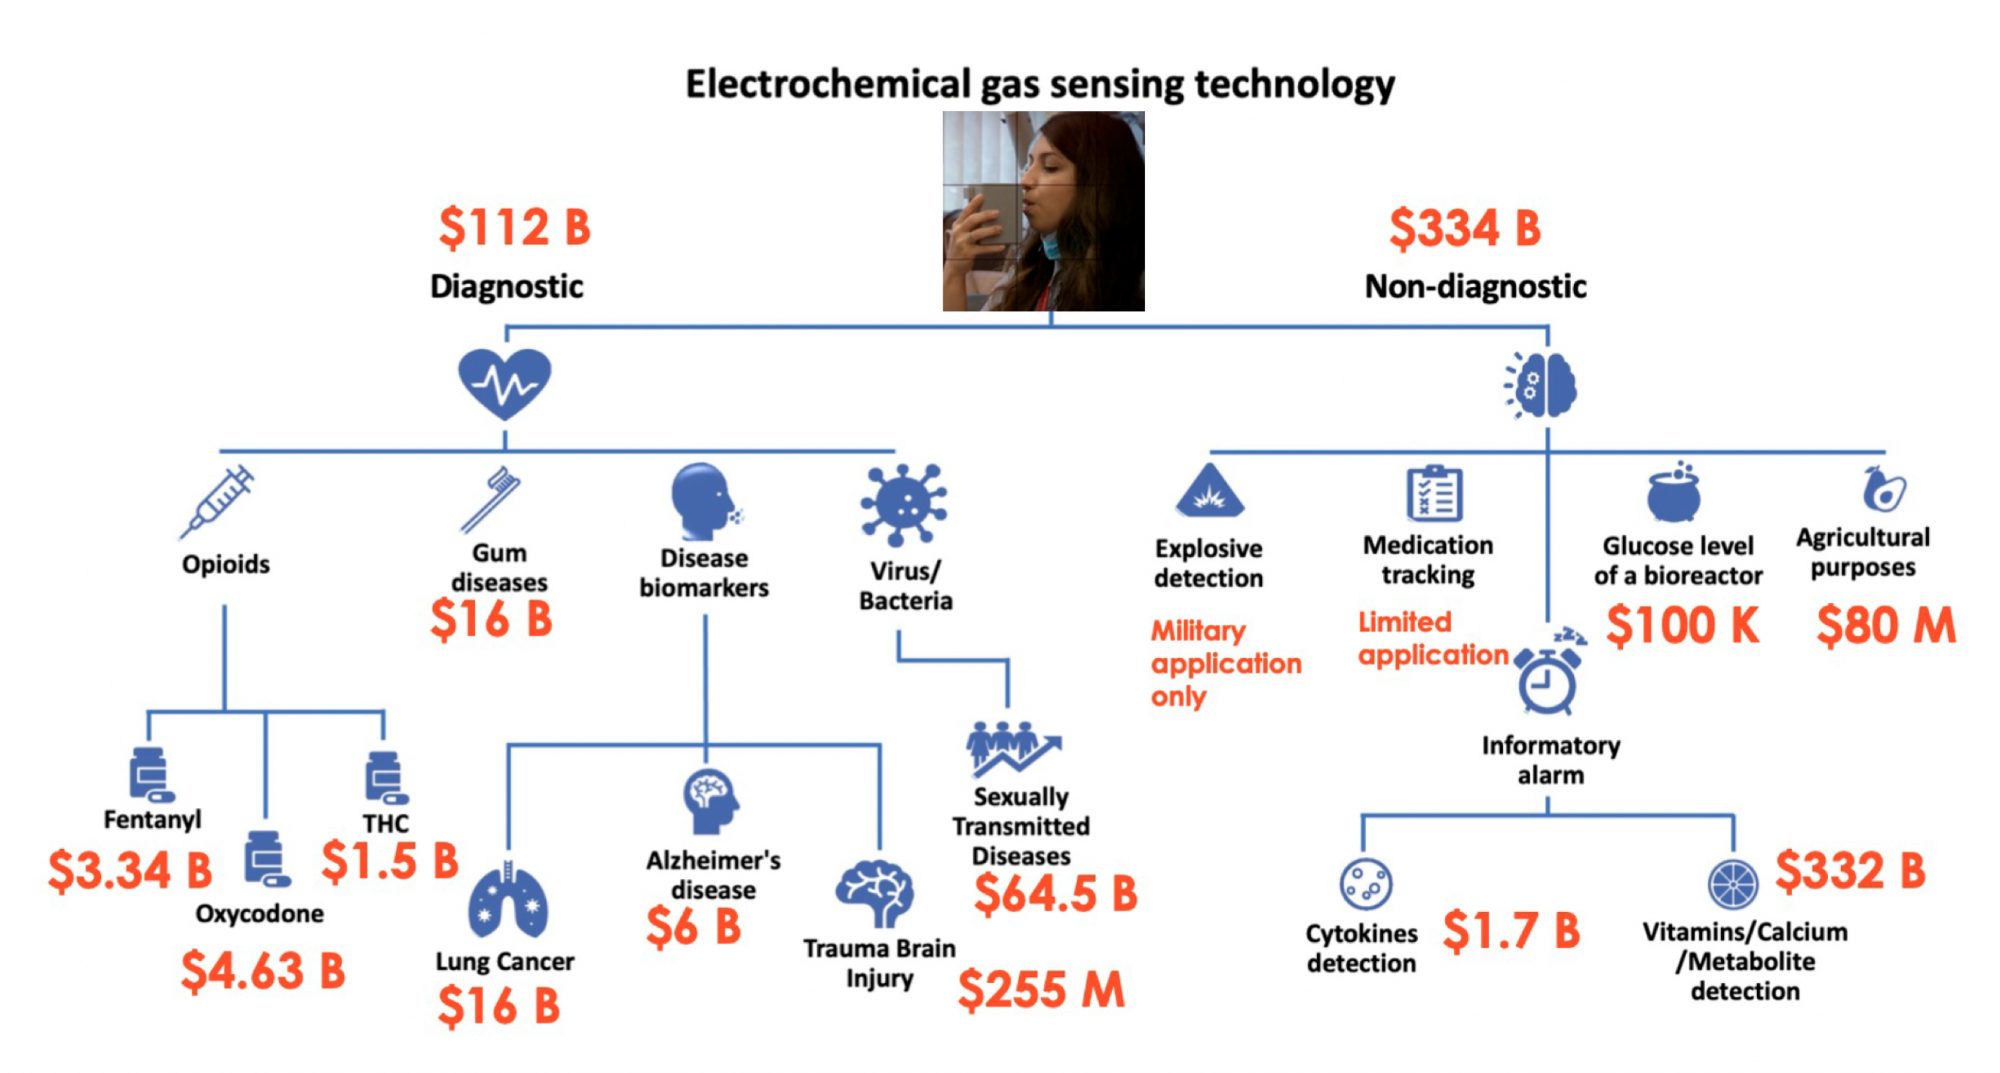

As another example, Professor Webster and his team have developed the concept of ‘Nano-optimizedTM’ where, based on prior implant success or failure and accompanied immune response, one can implement nanotextured features through AI to either ‘turn-on’ or ‘turn-off’ the immune system (Figure 3).

Or one can develop nanotextured features to inhibit bacteria colonisation if the patient has a weakened immune system or a history of implant infection. An example in Figure 3 is provided where tendon fixation devices were Nano-optimized to promote tendon growth, whereas today’s tendon fixation devices simply mechanically fix such tendons into bone. This is perfect technology for a patient with a history of orthopaedic soft tissue injuries.